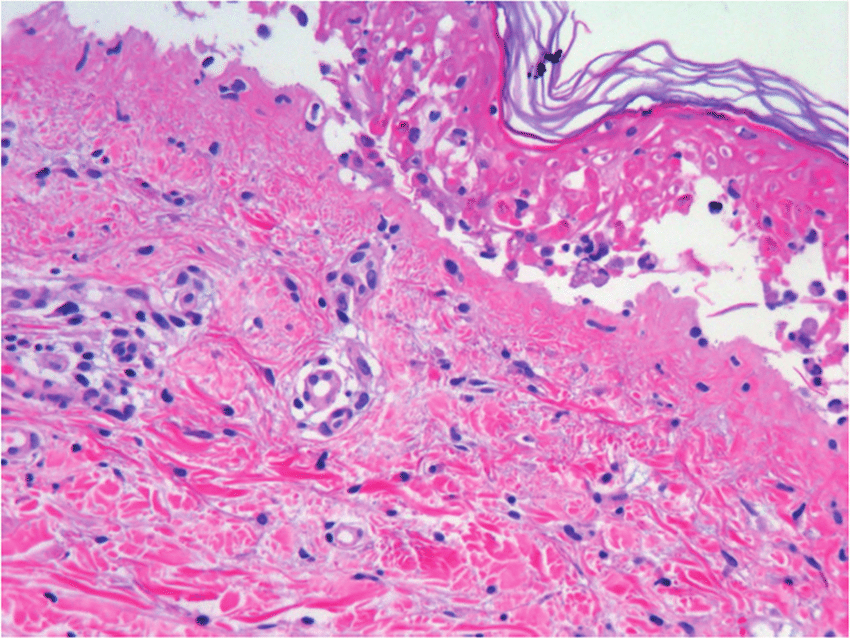

En general, su etiología y presentación son consensuadas, definiéndose como una necrólisis generalizada de la epidermis que se produce como una respuesta inmune descontrolada a un fármaco específico o a uno de sus metabolitos, destacando el cotrimoxazol y el alopurinol como los más importantes. Esta necrólisis conduce a un desprendimiento masivo de la capa epidérmica de la piel, con mayor incidencia en el torso, miembros superiores y cara. Eur. Burn J. 8 agosto 2022

La enfermedad de la piel inducida por fármacos o las reacciones cutáneas adversas a fármacos (RAMc) son términos que engloban las manifestaciones clínicas de la piel, las mucosas y los anexos inducidas por un fármaco o sus metabolitos. El reconocimiento de una reacciones cutáneas adversas a fármacos específica dependerá principalmente de la capacidad del médico para realizar un examen clínico detallado, la descripción adecuada de la morfología de las lesiones cutáneas y los hallazgos de laboratorio y/o biopsia de piel que respalden. Br J Clin Pharmacol, 16 de agosto de 2022